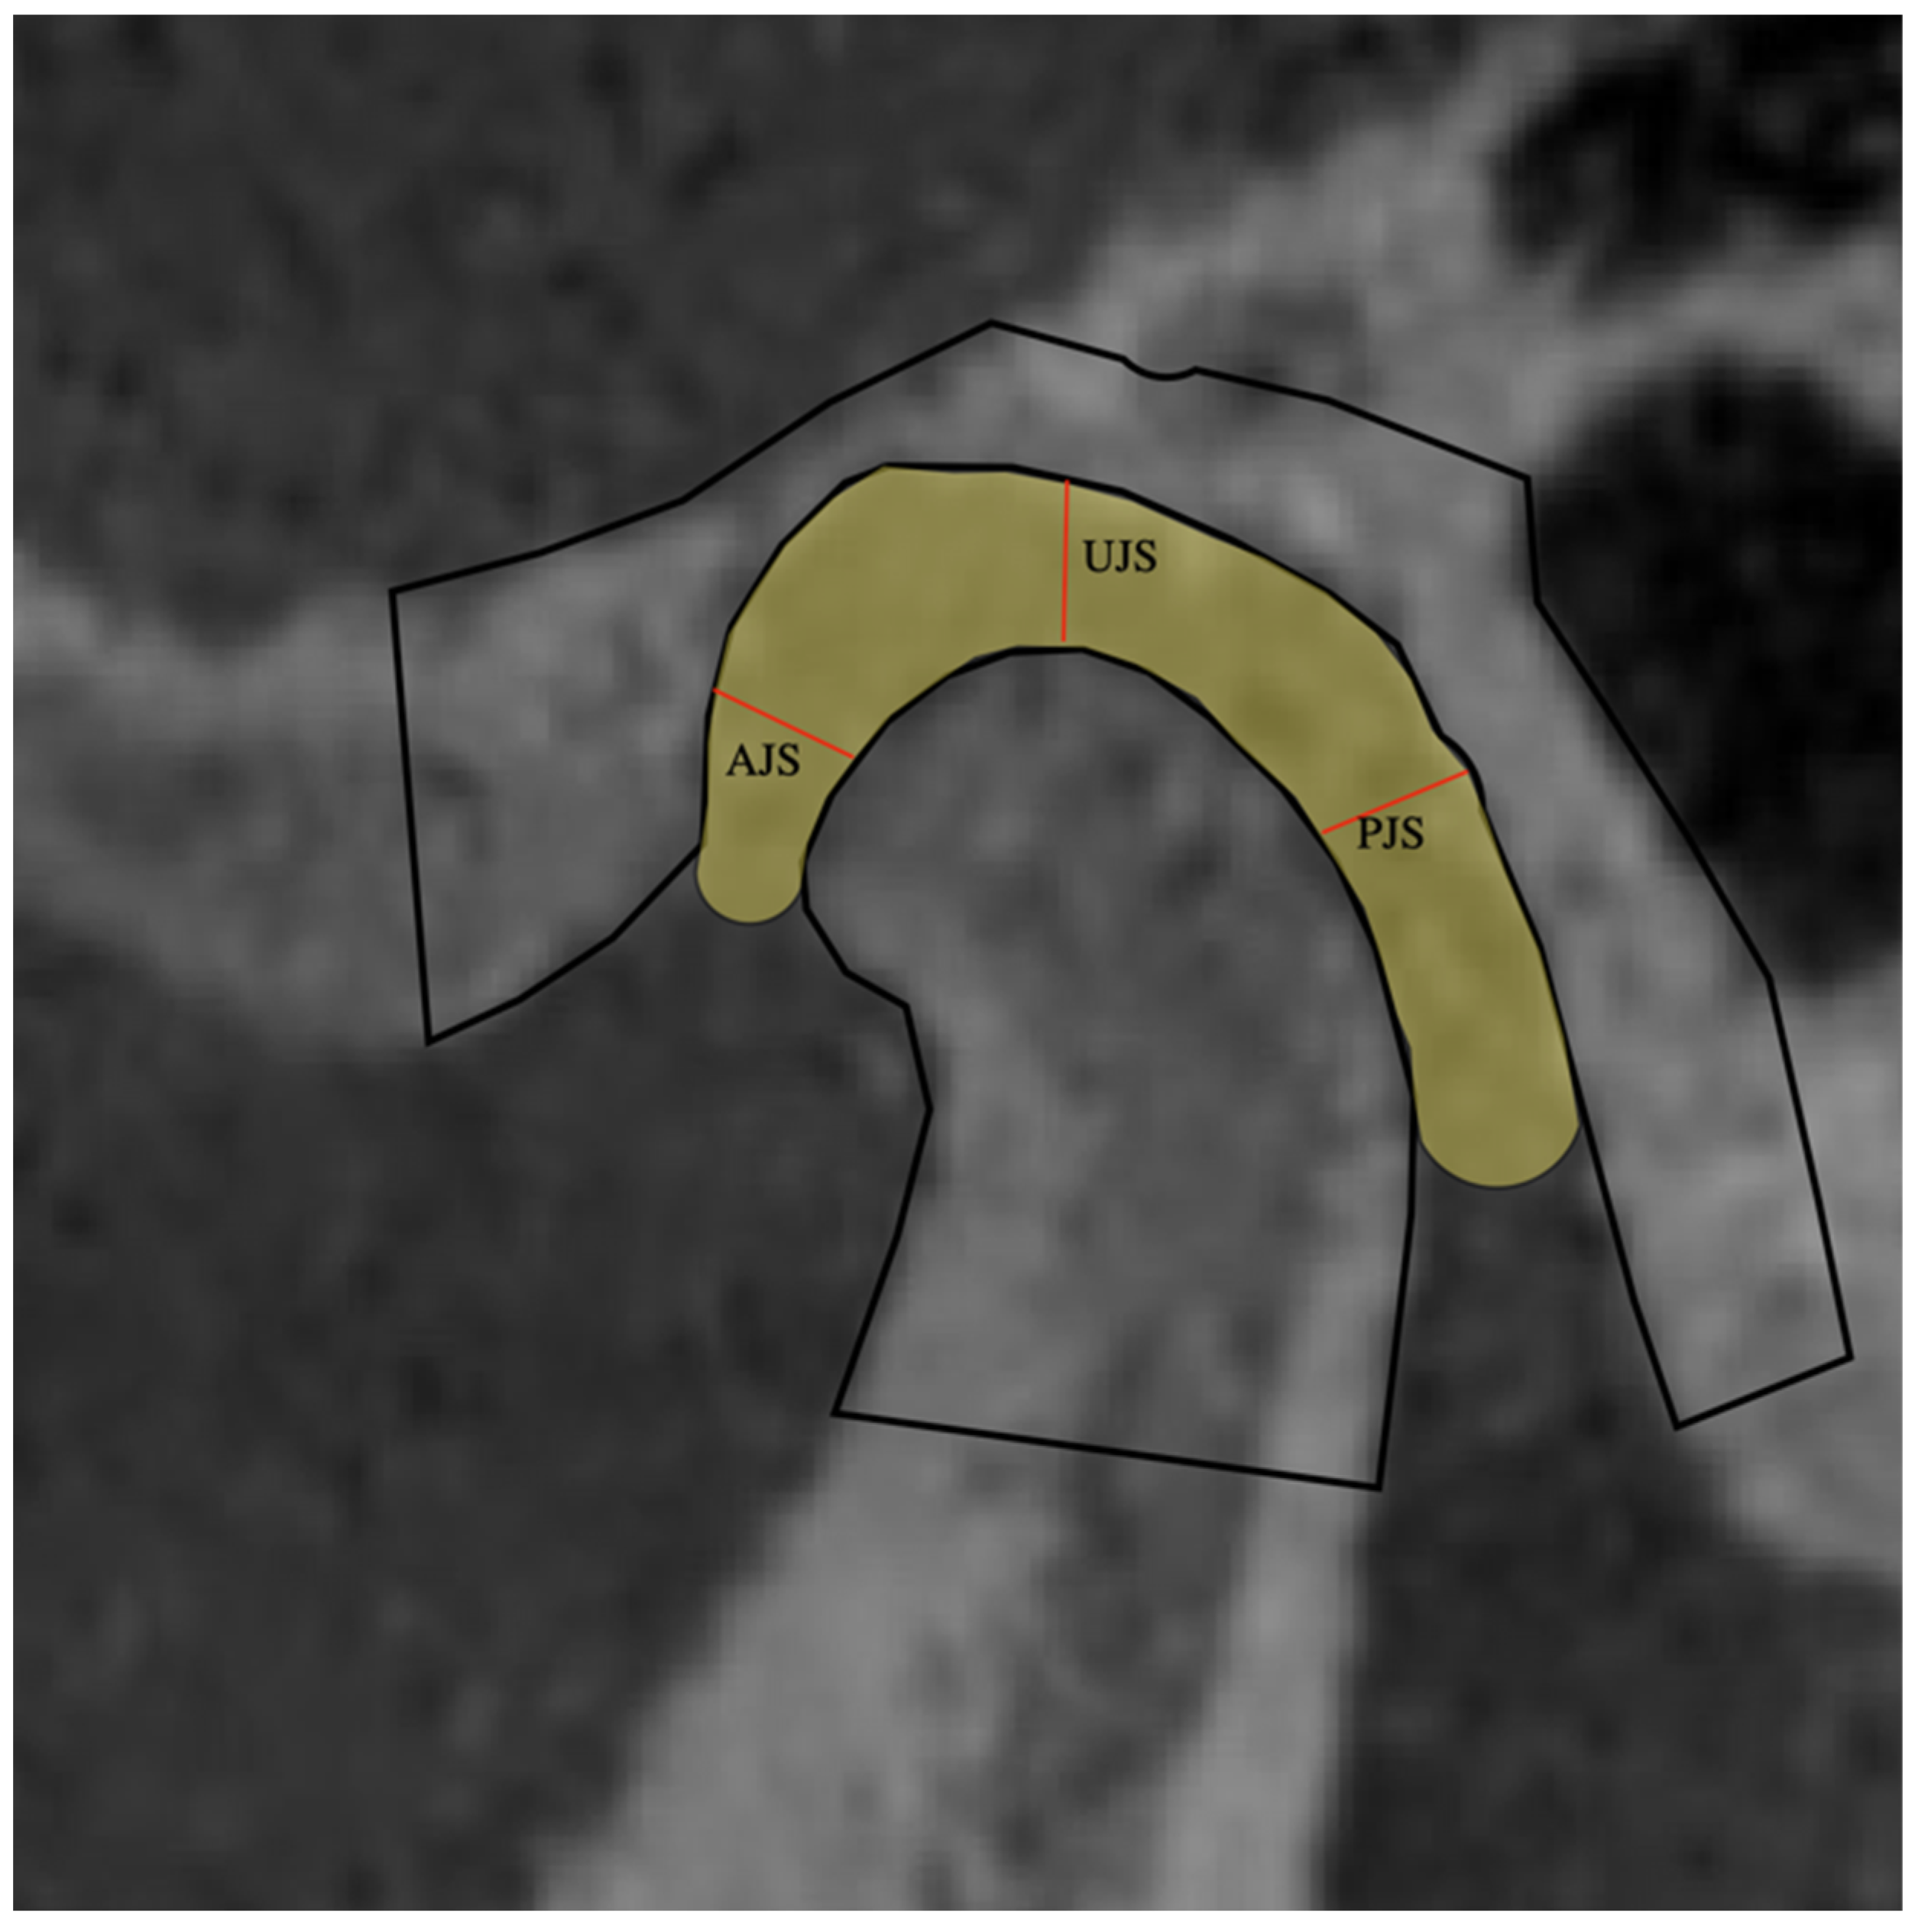

2.3. Joint Space (Sagittal Measurements)

2.4. Joint Space (JS) Average